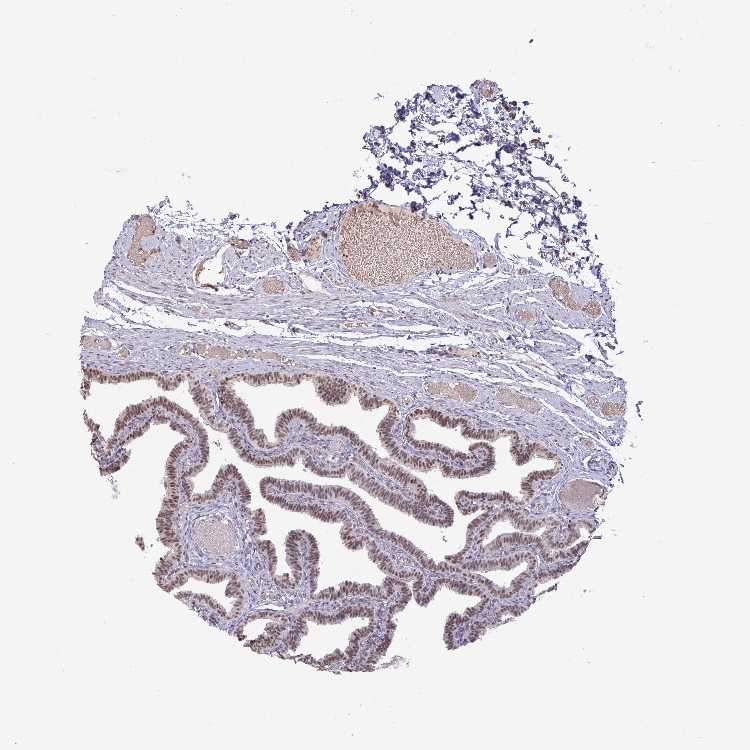

FALLOPIAN TUBE - Antibody stainingi

Antibody staining in the annotated cell types in the current human tissue is reported as not detected, low, medium, or high, based on conventional immunohistochemistry profiling in selected tissues. This score is based on the combination of the staining intensity and fraction of stained cells.

Each image is clickable and will lead to virtual microscopy that enables deeper exploration of all samples and also displays staining intensity scores, fraction scores and subcellular localization as well as patient and tissue information for each sample.

Antibody HPA052096Antibody HPA059714

Ciliated cells (cell body) Medium-

Ciliated cells (cilia axoneme) Not detected-

Ciliated cells (ciliary rootlets) Not detected-

Ciliated cells (tip of cilia) Not detected-

Glandular cells -Medium

Non-ciliated cells Medium-